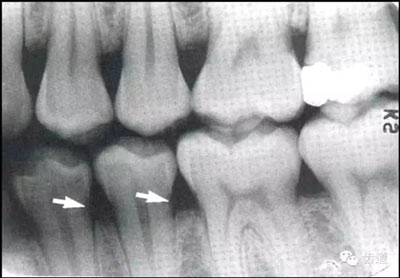

牙頸部Burnout征象:有時因投照技術(shù)問題而造成牙頸部近中或遠(yuǎn)中呈低密度影像,位于牙釉質(zhì)和牙槽嵴頂之間。